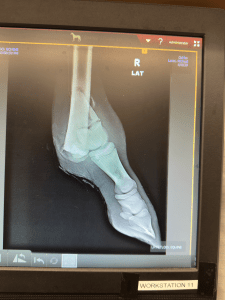

On day one under the surgeons care it was determined the little foals leg could likely be saved. The next 3 months in Cody, Wyoming were touch and go as the team at Yellowstone Equine Hospital controlled the infection and set Second Chance’s bones to fuse. It was a miracle in and of itself, but that was only the beginning. The rest of Second Chance’s healing journey was dependent on the care she would receive post Yellowstone. Now she needed to come home and settle in to beat the harsh Canadian winter.

However, Second Chance’s leg was still in a cast that needed to be changed regularly. Three hours from the nearest vet, this wasn’t an easy feat to tackle. Trailering her to the nearest vet would have to be a bi-weekly task, and that wasn’t feasible. With winter setting in, the best move to make was to wean her off her Dam Juno and bring her to a trusted friend and capable veterinarian. Dr. Ginger Langin with Dragon Lake Veterinary Hospital, six hours north of the ranch was the call.

While at Dragon Lake Vet, Second Chance has made fantastic progress. She gets stellar around the clock care including supplements, training and cast changes. When she exhibits healing to a point where she can full weight bear on her hoof and leg without a hard cast, she’ll be able to come home and reunite with her dam, Juno. We think we are close. But we still have to be set up at the ranch to X-ray, change casts and dressings to be able to properly care and support her

You and your family willingness to fight as long as Second Chance will to continued fighting. The xrays tell the store, the truth. Most would have ended it all. To spend the time making phone calls, asking questions, then traveling for days to safely transport her and her mom to Wyoming. Vet’s that were also willing to take on the challenge. Above and beyond, I am not sure you know any other way, to be honest. Second Chance looks unbelievable beautiful, strong and even after all that she has been through you can still see the fight in her sweet soft eyes. When you are around her…. she know you are her Hero and she shows you her love in her behavior around you.